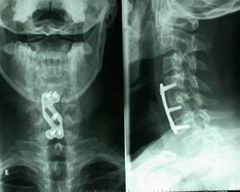

3、影像學檢查 X線平片可以顯示骨折及脫位情況。椎前陰影增寬。CT片可以顯示有無碎骨片移位。脊髓及其他軟組織的損傷範圍和程度需藉助MRI圖像。

3.影像學檢查 骨折及脫位的判定主要依據X線平片及CT掃描;但對軟組織損傷情況及脊髓狀態的判定,仍以MR圖像為清晰,應設法及早進行檢查。

其它輔助檢查骨折及脫位的判定主要依據X線平片及CT掃描;但對軟組織損傷情況及脊髓狀態的判定,仍以MRI圖像為清晰應設法及早進行檢查。